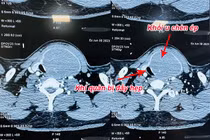

Bướu giáp thòng trung thất chiếm tỷ lệ nhỏ (3 – 20%) trong các trường hợp bướu giáp. Không chỉ xâm lấn hai thùy giáp, thực quản và khí quản, loại bướu này còn thòng xuống lồng ngực, chèn ép các mạch máu quan trọng...

Người bệnh bị bướu cổ hơn 30 năm với kích thước khối u tuyến giáp lớn, chèn ép, đẩy khí quản cổ sang một bên gây khó thở đã được các bác sỹ Bệnh viện Nhân dân Gia Định phẫu thuật thành công.

Bị u tuyến giáp lành tính to không mổ, đến khi nuốt vướng mới đến lại bệnh viện thì u vỡ, chèn ép khí quản, thần kinh thanh quản và thực quản gây nguy hiểm tới tính mạng.

Các bác sĩ Bệnh viện TWQĐ 108 vừa phẫu thuật thành công khối u tuyến giáp khổng lồ với kích thước thùy phải 10x6cm, kích thước thùy trái 12x7cm, phát triển cả lên phía trên và đẩy xuống nền cổ, gây đè hẹp khí quản.